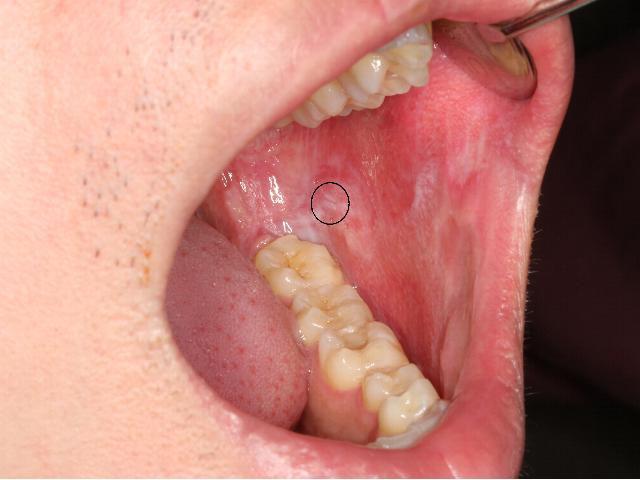

〔記者吳玉芬/嘉義市報導〕45歲的許小姐,從事餐飲業,工作壓力大所以常有抽菸的習慣,平時自認無咳嗽等症狀,日前在醫院護理師建議之下接受免費口腔黏膜篩檢,經檢查發現左側頰部有一塊範圍約兩公分大小的「紅斑」,於是醫師就進行雷射切除紅斑,切片報告赫然發現在病灶中竟有癌細胞。許小姐驚嚇之餘趕緊接受後續檢查,確診為第一期口腔癌,所幸在經過口腔癌手術後,定期門診追蹤,一年下來恢復良好。

國人十大死因中,惡性腫瘤(癌症)死亡率仍高居第一位,天主教聖馬爾定醫院口腔顎面外科醫師陳建晟表示,在今年亞太口腔顎面外科醫學會年會報告中,以疣狀增生及非均質白斑轉變為癌症的機率較大。國民健康署近年來持續推廣癌症篩檢:子宮頸癌、乳癌、大腸癌及口腔癌,這四種癌症有實證經由篩檢可以早期偵測到初癌,這位許小姐便是透過篩檢,早期發現、早期治療的最佳案例。

由於是口腔癌第一期,所以手術後不需要接受進一步的放射治療或化學治療,大大減少了患者的痛苦及家庭負擔,也降低了癌症遠端轉移的風險及死亡率,顯見口腔癌篩檢的重要性。為響應「12月3日檳榔防制日」,聖馬爾定醫院特別免費提供「專人服務陪同」口腔癌篩檢服務,民眾可攜帶健保卡至醫院一樓的癌症篩檢中心或口腔顎面外科的門診掛號,由專科醫師進行口腔篩檢,若發現癌前病變(如白斑、紅斑),皆能盡速切片檢查及確診。

以聖馬爾定醫院口腔篩檢為例,今年1662人中篩檢陽性率為4.81%,特別是嚼食檳榔、喝酒及抽菸的高危險群,罹患口腔癌的機率竟達123倍,更應定期接受口腔癌篩檢。其中檳榔有多種致癌因子,會導致口腔黏膜下纖維化,致嘴巴張不開、口腔灼熱感,有致癌危險,建議如有以上症狀應盡速至醫院就診。